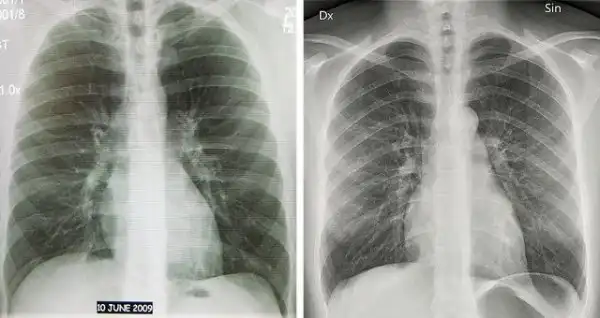

4. Флюорография и рентген легких

Оба варианта являются методами диагностики, но имеют некоторые различия в качестве.

Флюорография дает уменьшенное изображение объекта и заболевание видно хуже, чем на рентгеновском снимке. Флюрография показывает только легкие и часть сердца.

Рентген позволяет увидеть контуры легких, мягкие ткани, сердце, кровеносные сосуды и костные структуры.